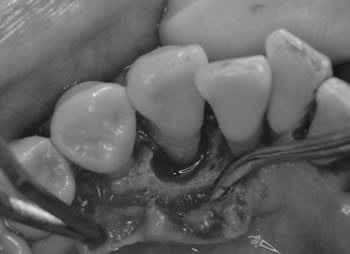

術中

歯の周りには骨が破壊され、感染源も残っていました。